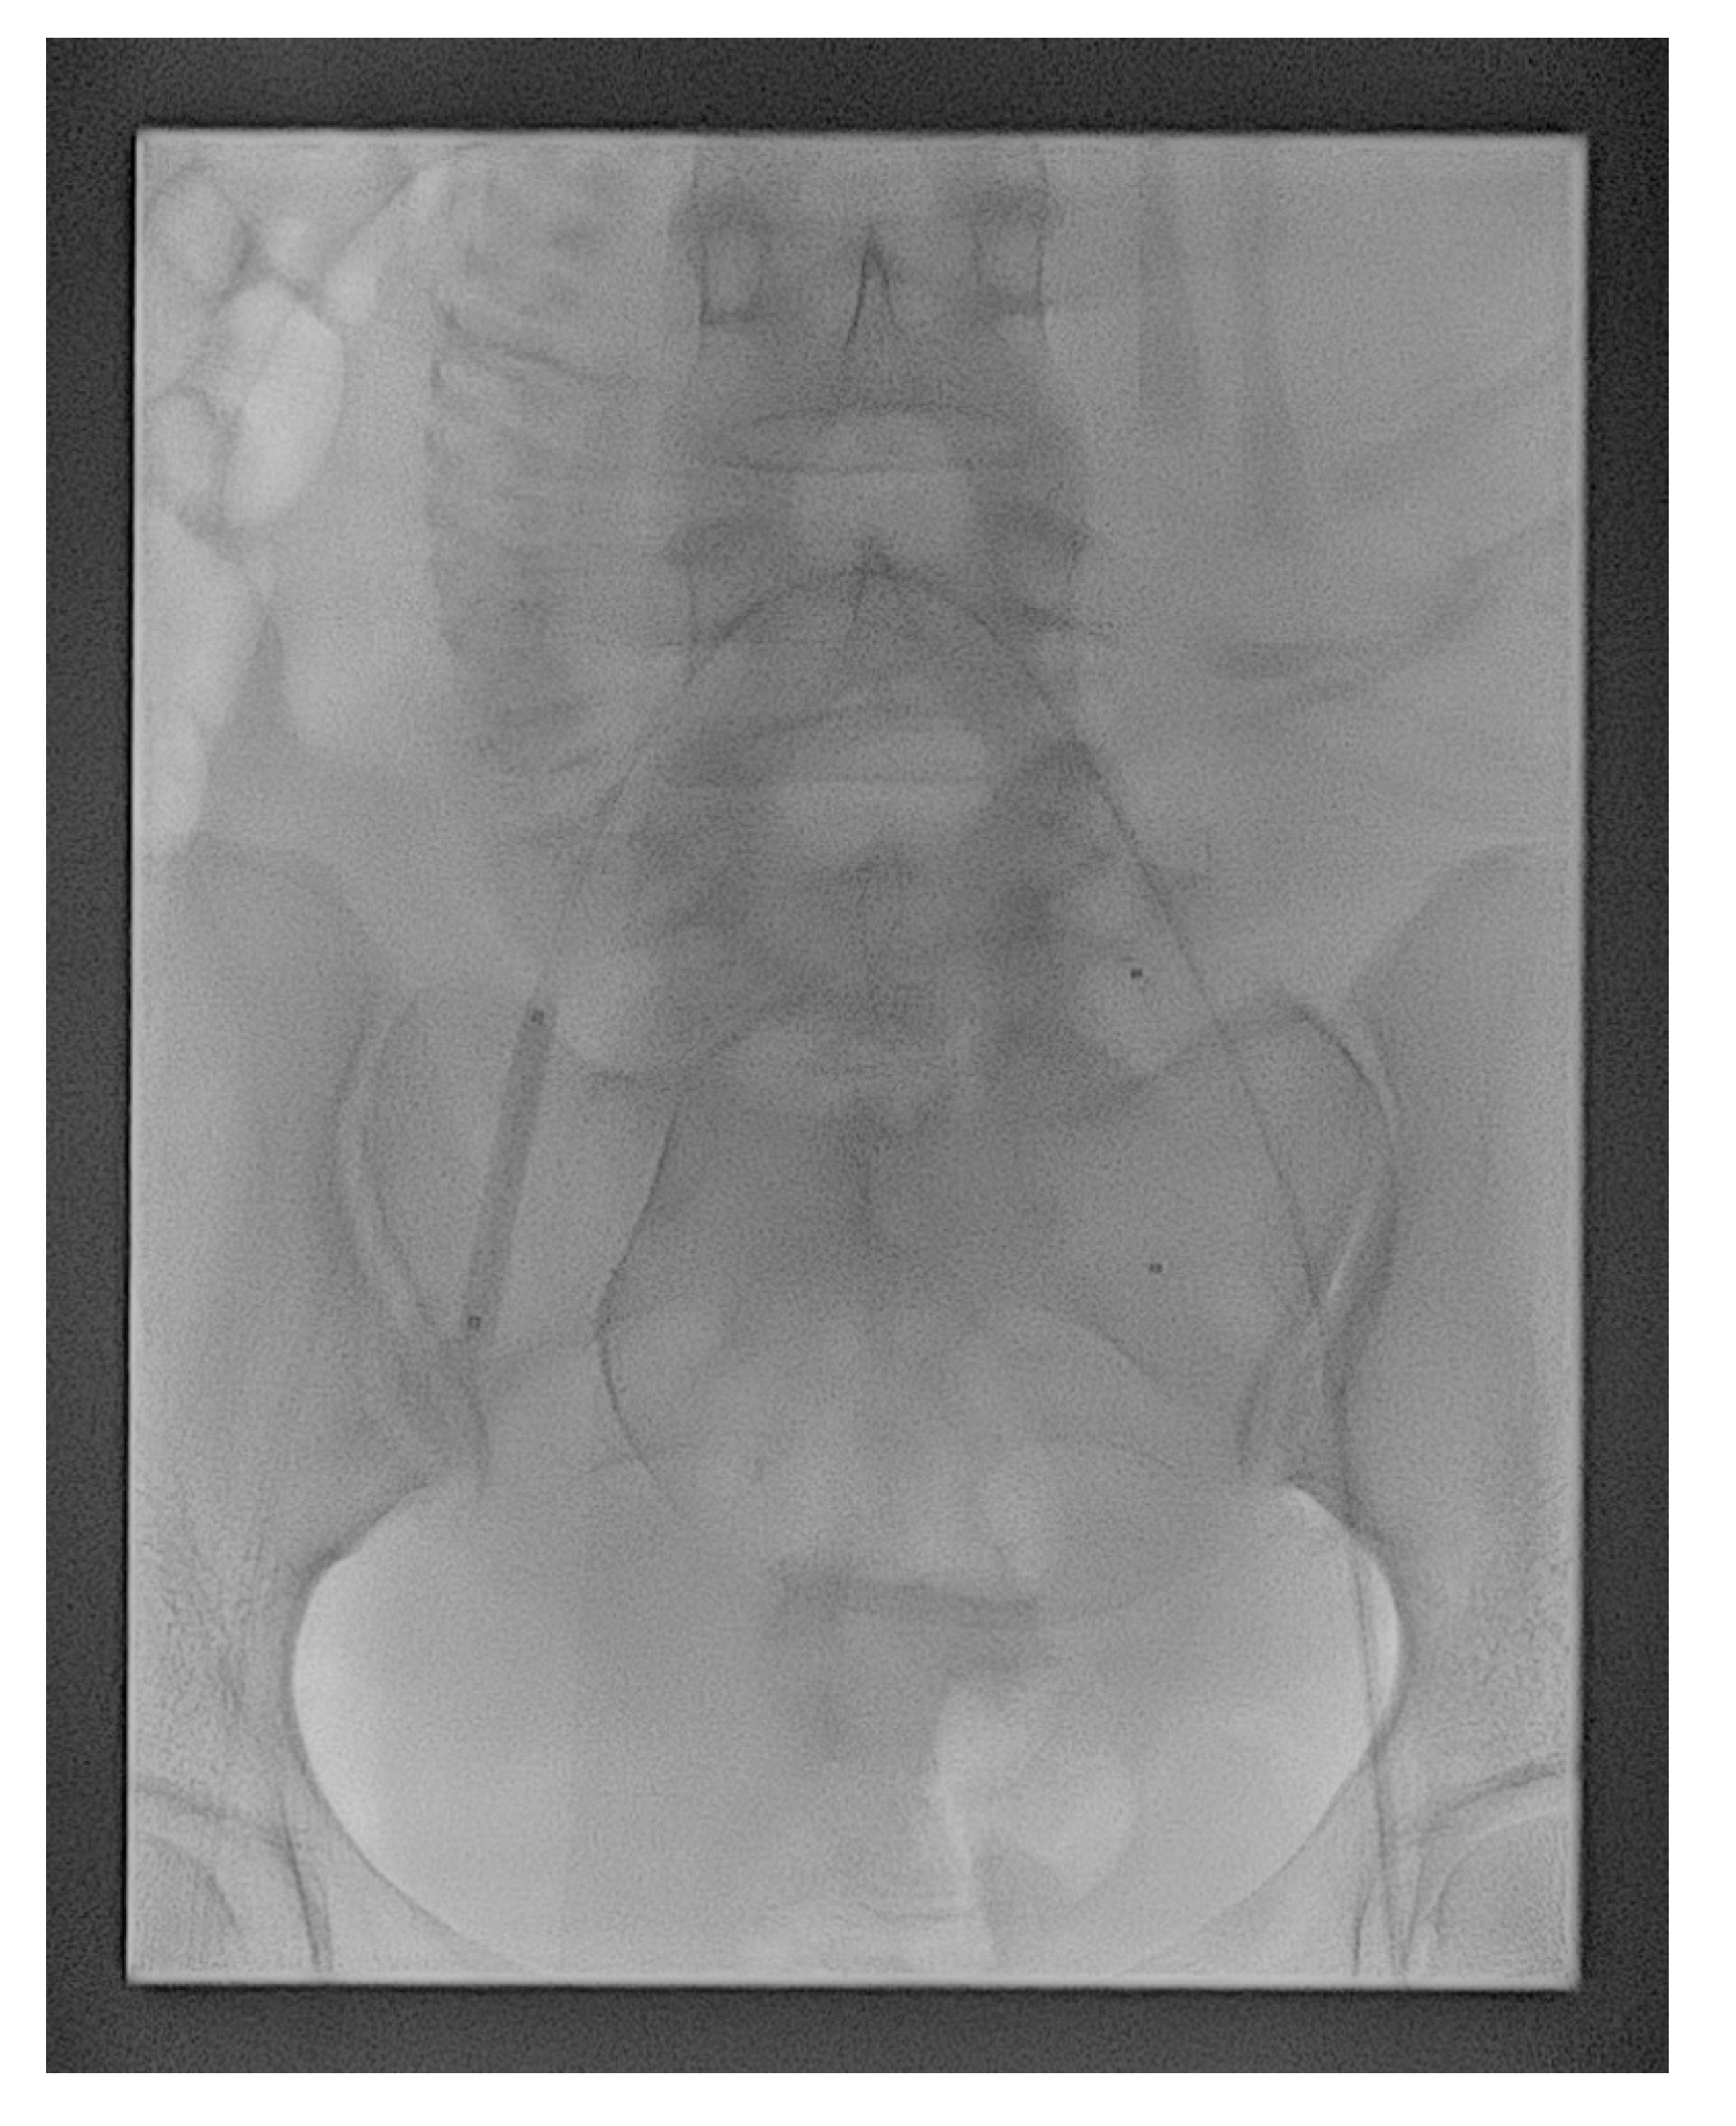

On the day of delivery, patients were taken to the interventional suite for PBAO, bilateral common femoral arterial puncture, and access of the 6-Fr vascular sheaths under local anesthesia. Both the internal iliac arteries were cannulated using a contralateral approach, with a 5-Fr reverse curve catheter (Yashiro; Terumo, Tokyo, Japan or UAC; Merit Medical, Jordan, UT, USA). This was exchanged for a 6- or 7-mm-diameter, 40-mm-long, standard percutaneous transluminal angioplasty balloon catheter (Mustang; Boston Scientific, Galway, Ireland), which was positioned with its tip in the proximal portion of the contralateral internal iliac artery, just after the common iliac artery bifurcation (Figure 1). Arterial diameter measurement was performed at the time of balloon insertion to ensure correct balloon sizing. We found that 1 mL (6-mm × 40-mm) and 1.5 mL (7-mm × 40-mm) of contrast media were generally sufficient for artery occlusion. The exact same volume was subsequently used to inflate the balloons, hence eliminating the need for additional fluoroscopic exposure during cesarean delivery. The catheters were securely taped to the skin, and the sheaths were sutured in place, with a transparent dressing placed over them to further ensure stability.

Figure 1. Fluoroscopy showing the balloon catheters positioned in the main lumen of the internal iliac arteries bilaterally. The balloon catheter of the right internal iliac artery was inflated as a test.